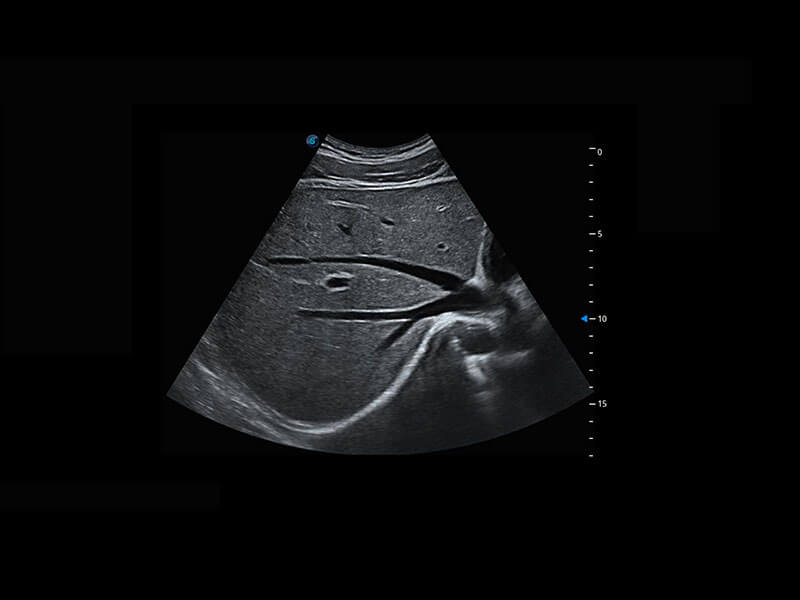

胎儿体循环

P60搭载一系列胎儿心脏成像技术,实现精细的胎儿心脏评估。

四腔切面

四腔心血流

右室双出口

胎心容积成像